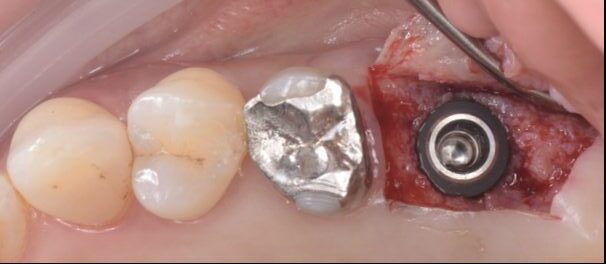

インプラントを埋入

仮歯の試適を行い